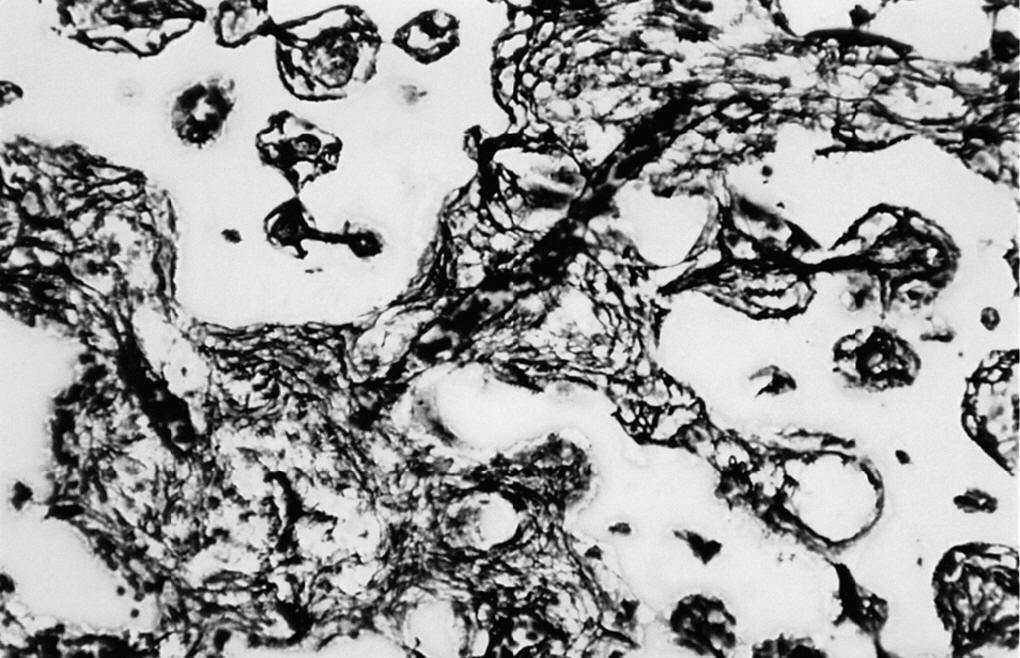

Estudio morfológico. En este grupo observamos la formación de hueso en uno de los bordes laterales del material implantado, que conectaba la cortical interna con la contralateral. Tanto alrededor del implante como en el interior de los poros se observaron escasos restos de tejido de granulación (15% aproximadamente). Asimismo, existía una sustitución de alrededor del 80% del material implantado por abundantes trabéculas óseas neoformadas de morfología irregular, que periféricamente lo envolvía en su totalidad, mientras que en las porciones centrales se observaron pequeñas trabéculas en íntimo contacto entre sí (fig. 6).

Figura 6. Detalle de la trama reticulínica (*) y vasos (v) que comunican los poros del implante entre sí (c) (Gordon Sweet, 500 x).

Mediante el MEB comprobamos que la mayor parte del volumen del implante estaba colonizado por tejido óseo maduro, persistiendo áreas ocupadas por osteoide (fig. 7).

Figura 7. Tejido de granulación y material osteoide ocupando los poros del implante (750 x).